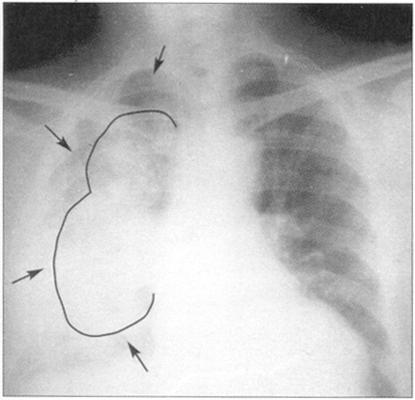

左心衰或肺水肿表现为肺部X光片上出现蝴蝶征(图35)。

图35 胸部X线显示肺水肿(蝙蝠翅膀),右侧更明显